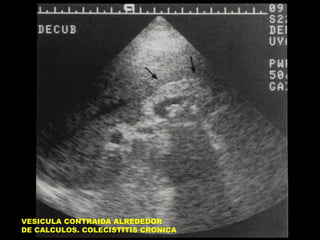

VESICULA CONTRAIDA ALREDEDOR DE

CALCULOS. COLECISTITIS CRONICA